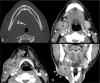

Inflammatory and obstructive disorders of the salivary glands are caused by very different pathological conditions affecting the gland tissue and/or the excretory system. The clinical setting is essential to address the appropriate diagnostic imaging work-up. According to history and physical examination, four main clinical scenarios can be recognised: (1) acute generalised swelling of major salivary glands; (2) acute swelling of a single major salivary gland; (3) chronic generalised swelling of major salivary glands, associated or not with "dry mouth"; (4) chronic or prolonged swelling of a single major salivary gland. The algorithm for imaging salivary glands depends on the scenario with which the patient presents to the clinician. Imaging is essential to confirm clinical diagnosis, define the extent of the disease and identify complications. Imaging techniques include ultrasound (US), computed tomography (CT) and magnetic resonance (MR) with MR sialography.